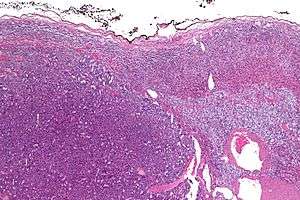

Micrograph of an adrenocortical carcinoma (left of image – dark blue) and the adrenal cortex it arose from (right-top of image – pink/light blue). Benign adrenal medulla is present (right-middle of image – gray/blue). H&E stain. | |